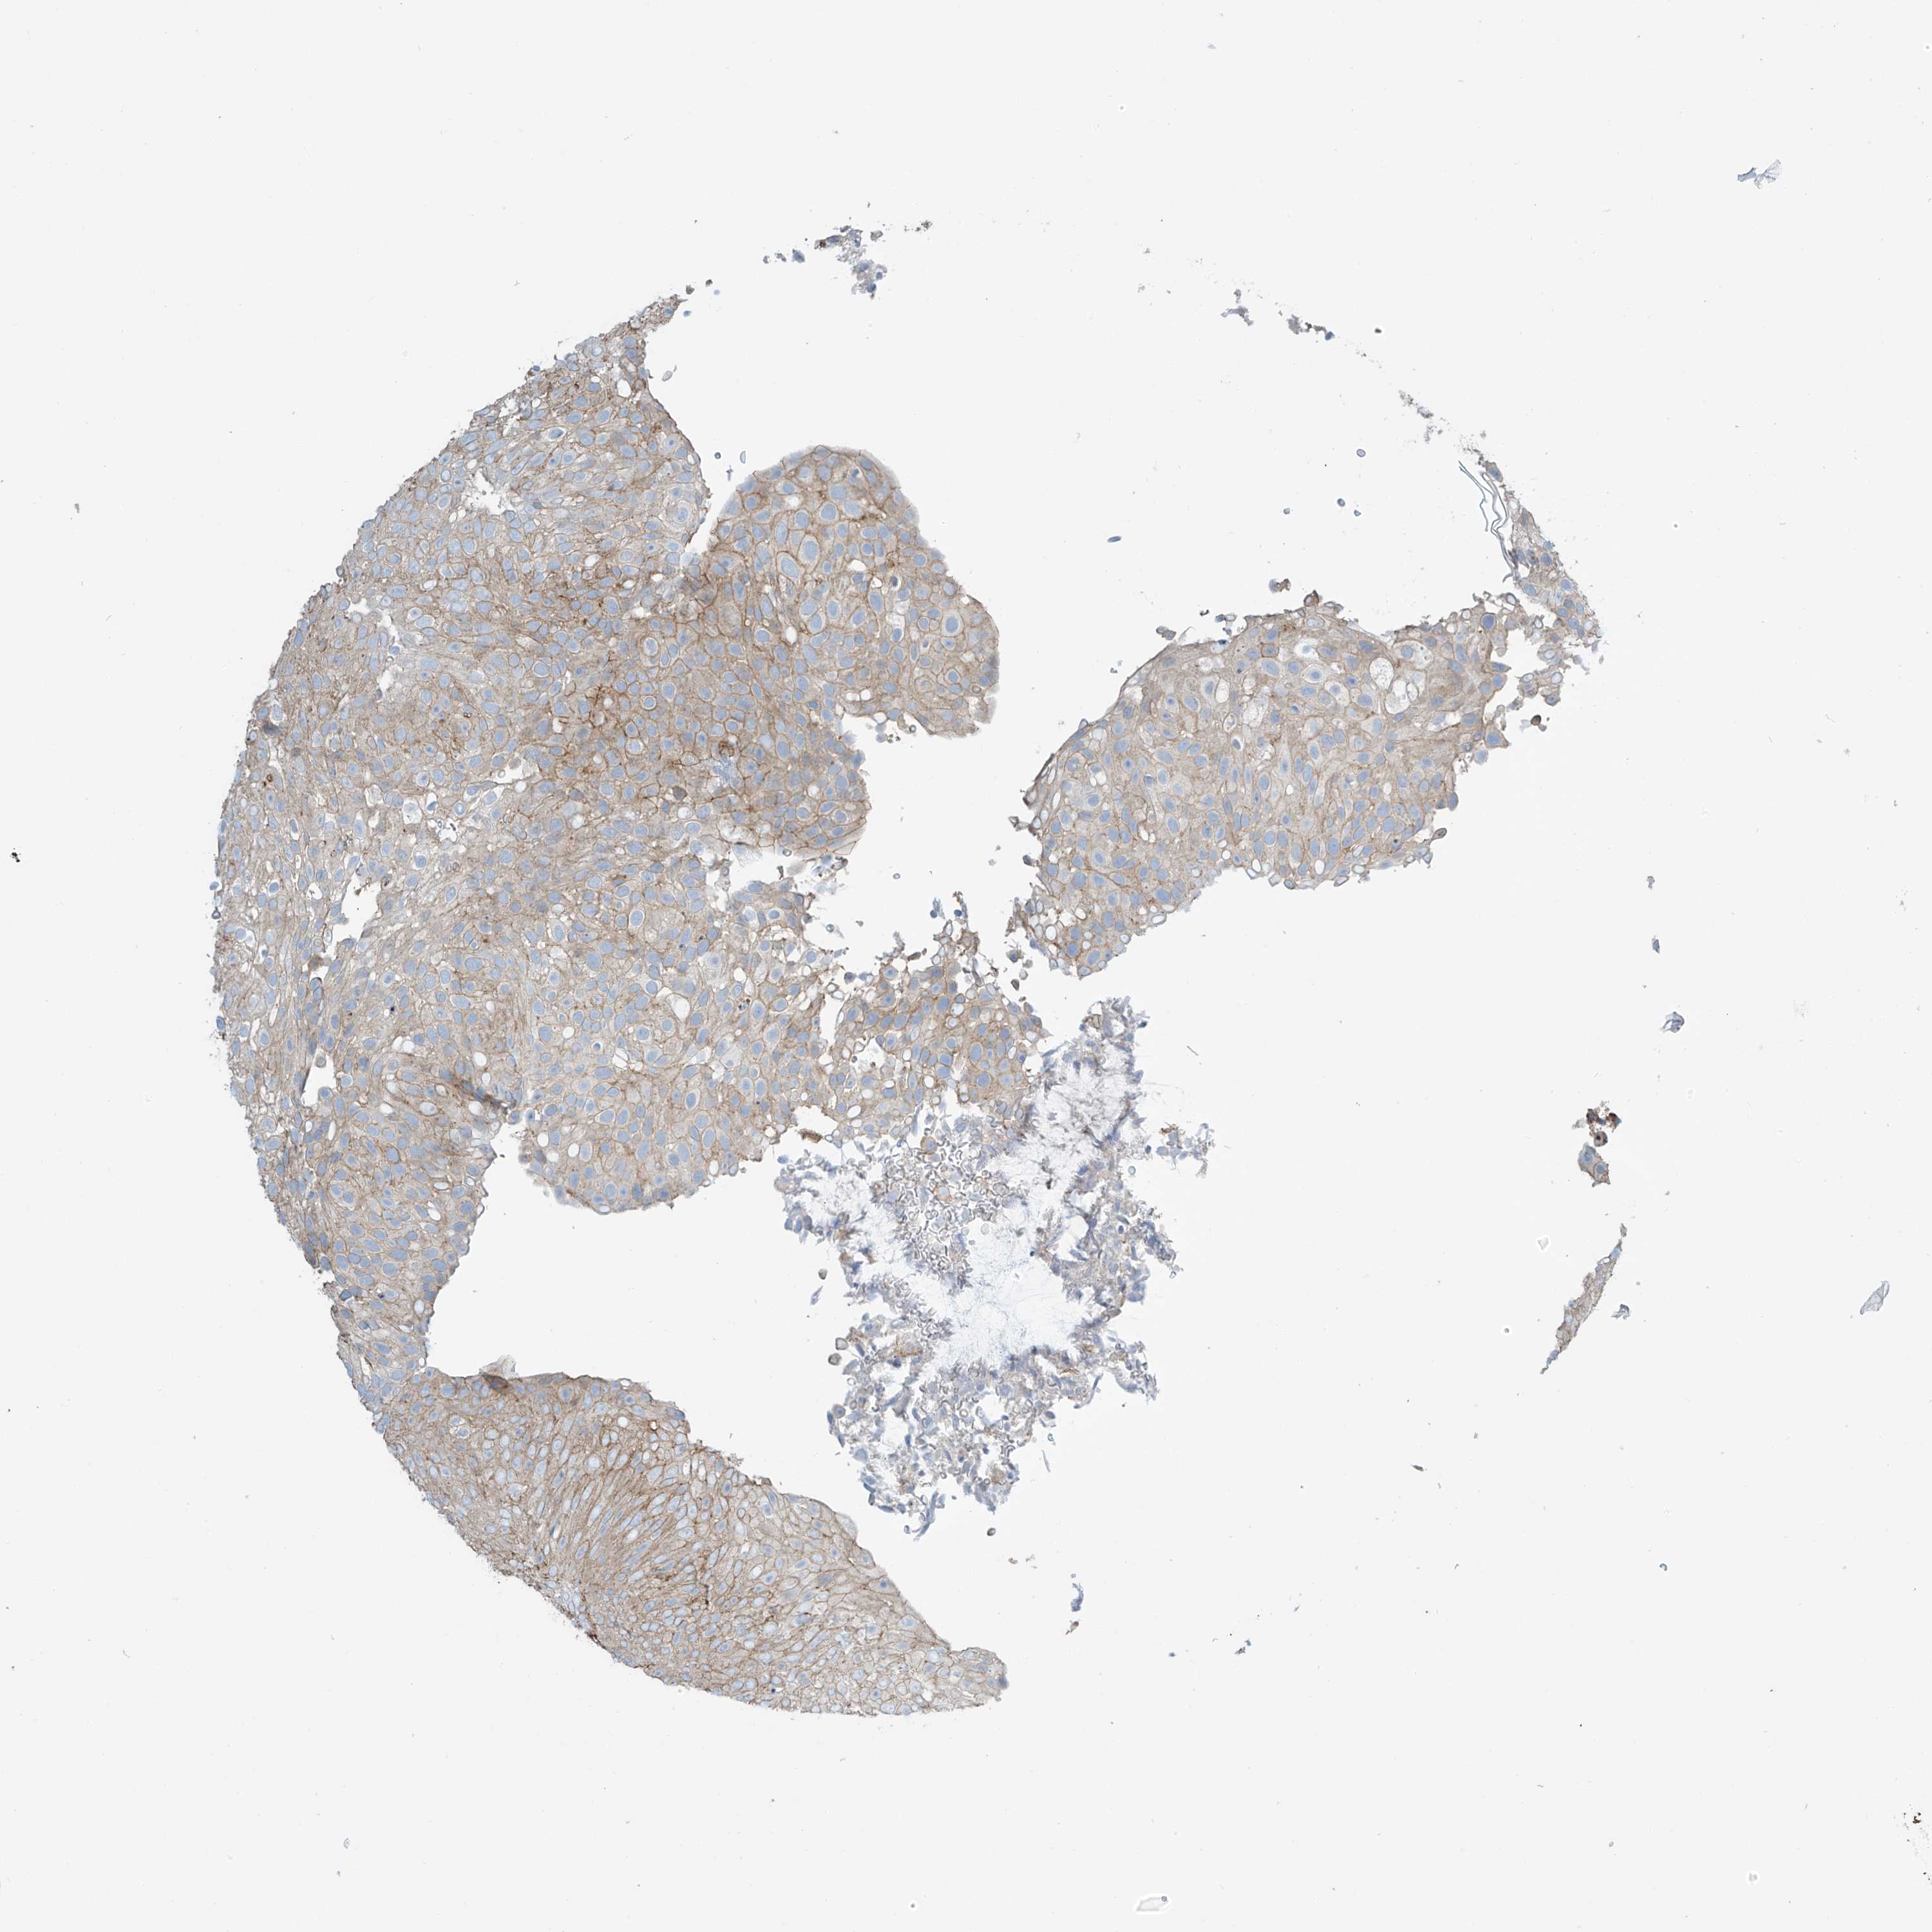

UROTHELIAL CANCER - Protein expressioni

A mouse-over function shows sample information and annotation data. Click on an image to view it in a full screen mode. Samples can be filtered based on level of antibody staining by selecting one or several of the following categories: high, medium, low and not detected. The assay and annotation is described here.

Note that samples used for immunohistochemistry by the Human Protein Atlas do not correspond to samples in the TCGA dataset.

Antibody stainingi

Antibody staining in the annotated cell types in the current human tissue is reported as not detected, low, medium, or high, based on conventional immunohistochemistry profiling in selected tissues. This score is based on the combination of the staining intensity and fraction of stained cells.

Each image is clickable and will lead to virtual microscopy that enables deeper exploration of all samples and also displays staining intensity scores, fraction scores and subcellular localization as well as patient and tissue information for each sample.

Antibody HPA035121

Antibody HPA035122

Staining

High

Medium

Low

Not detected

Intensity

Strong

Moderate

Weak

Negative

Quantity

>75%

75%-25%

<25%

None

Location

Nuclear

Cytoplasmic/membranous

Cytoplasmic/membranous,nuclear

Urothelial carcinoma, High grade

Urothelial carcinoma, Low grade